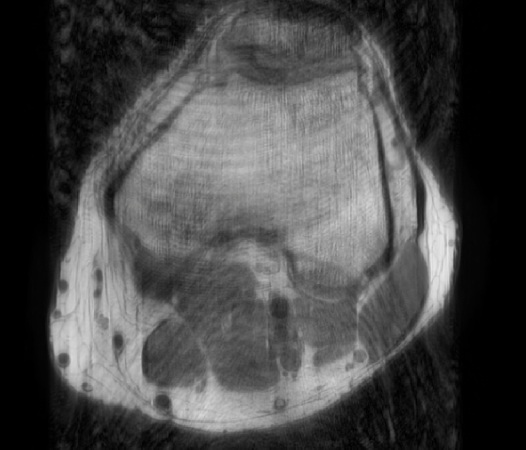

In the example below, only one fifth of the required MR radiofrequency signals is recorded. This results in a five times faster acquisition, with a subsampled k-space (top left) and inherent image artifacts after standard reconstruction (top right).

Knee with artifacts

The Compressed SENSE reconstruction then uses iterative, knowledge-based algorithms to fill in the empty lines in k-space (bottom left). This removes the artifacts while keeping the final image fully consistent with the acquired data (bottom right).